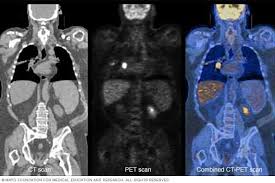

Positron Emission Tomography PET is a medical imaging technique that allows us to see what is happening in the body at a cellular level. Brain 2250 10700. Conlu MD Nuclear Medicine-PETCT 09178278445.

Pgh pet scan price. The CT component can determine the tumors exact location size and configuration. NKTI PETCT Centers introductory price. Gomez MD PET-CT Radiologist.